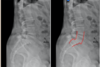

spotting spondylolysis

- Trace the outline of scottie dog in oblique view of the spine

- Displaced fractures through the pars interarticularis (i.e. spondylolysis), look like a collar on a dog (look at blue outline)

X-ray of spondylosis